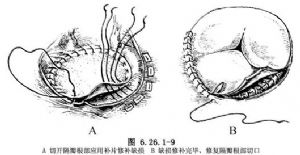

③隔瓣下缺損修補方法:隔瓣下缺損又稱房室管型室間隔缺損,該部位缺損常被三尖瓣隔瓣掩蓋。於三尖瓣隔瓣置2根牽引線,牽開三尖瓣隔瓣多可顯露其下方缺損。假如掩蓋室間隔缺損的瓣葉或腱索無法牽開,可於三尖瓣隔瓣根部距瓣環2~3mm處切開三尖瓣,並將切開瓣葉牽往前方,隔瓣下方缺損即得到良好顯露(圖6.26.1-8)。三尖瓣隔瓣直接與缺損相鄰,頭、尾側分別爲鬥隔和小梁隔,以及右室流入道間隔。頭側三尖瓣隔瓣裂常指向中央纖維體,三尖瓣下方室間隔缺損後下緣有傳導束經過,穿越中央纖維體後分爲左右束支,左束支在室間隔左室面內膜下行走,右束支在室間隔膜部下方分出後,於右室面心內膜下向前進入調節束抵達前乳頭肌基部。圖6.26.1-8插圖顯示了冠狀靜脈竇、房室結,房室束和束支走行與室間隔缺損關係。應用帶墊片和褥式縫線於缺損後下緣做5~6間斷褥式縫合,鄰近三尖瓣環處的縫線縫於三尖隔瓣根部,其他部位縫線緣縫於室間隔的右室側,以免損傷傳導束。上述縫線分別穿過補片相應邊緣並結紮(圖6.26.1-9A)。然後以5-0無創縫線縫合切開的三尖瓣(圖6.26.1-9B)。然而大多數情況下閉合此類缺損可不需切開三尖瓣葉,僅需牽開三尖瓣隔瓣,顯露和修補隔瓣下缺損(圖6.26.1-10)。